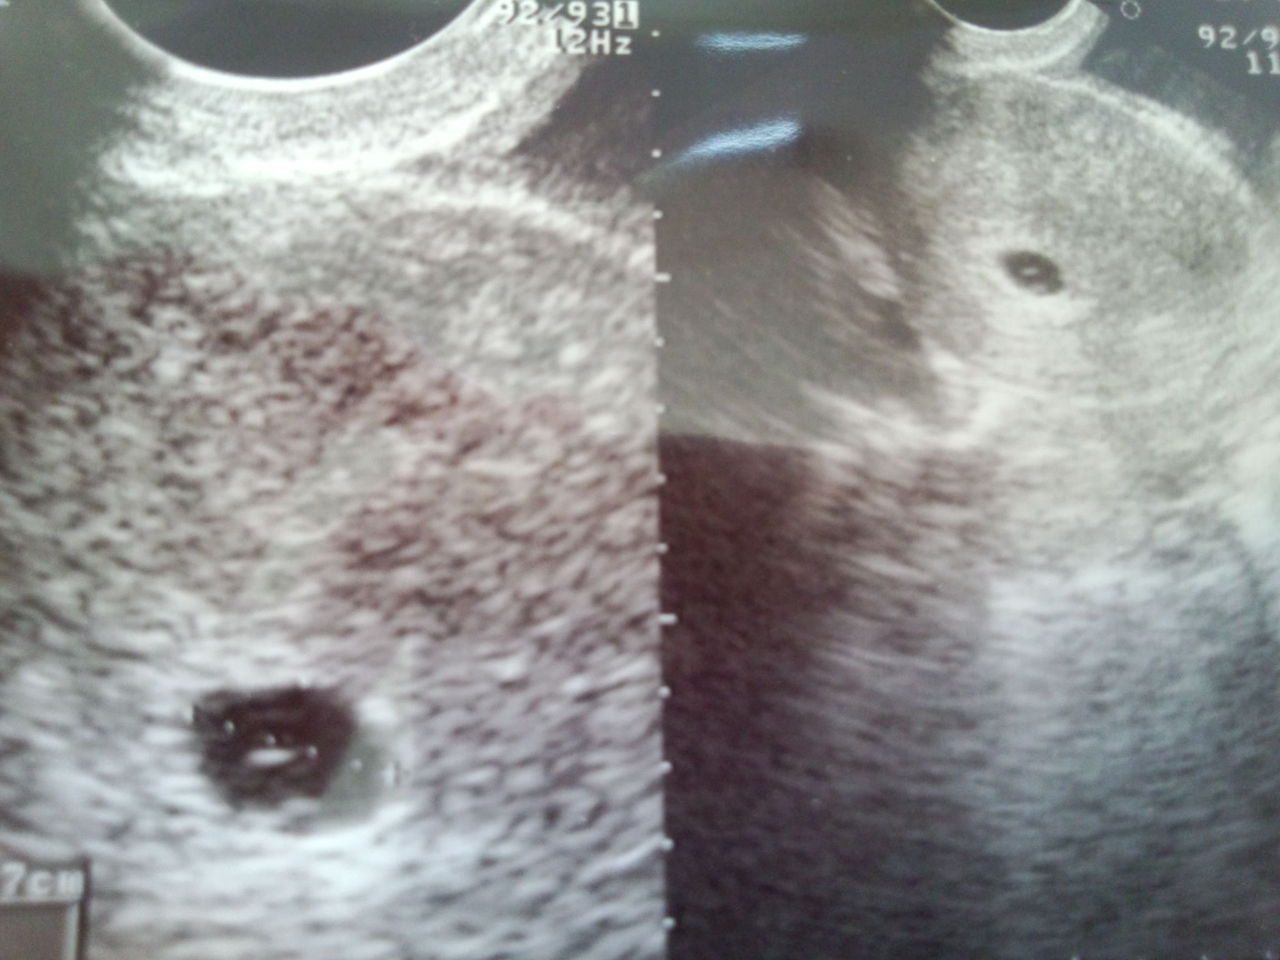

高温期30日目、いよいよ初診。6wぐらいかと思ったら、、、